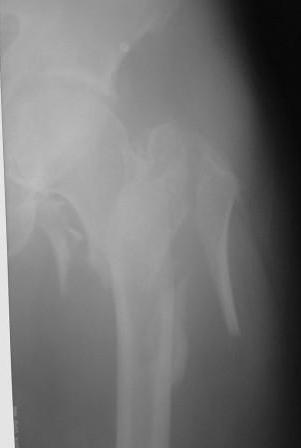

Прилагаю Р-ы на вытяжении.

>Прилагаю Р-ы на вытяжении.

По нашему мнению линия перелома проходит вверху через латеральный отдел шейки бедра, вертельная область состоит из нескольких фрагментов. В таких условиях применить DHS или дистальную бедренную пластину LCP представляется нам сомнительным. Закрытый остеосинтез проксимальным гамма-гвоздем или PFNa невозможен т.к. нет ЭОПа.